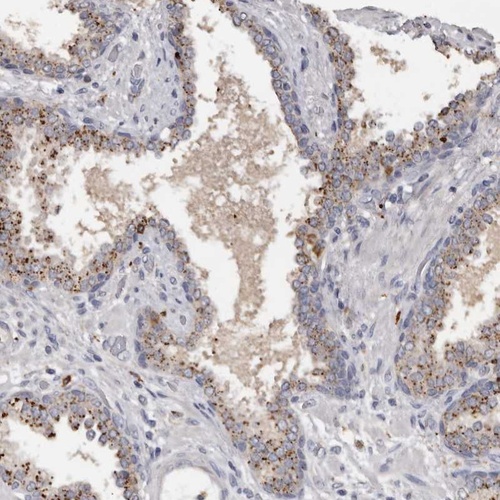

Immunohistochemical staining of human prostate shows moderate granular positivity in glandular cells.